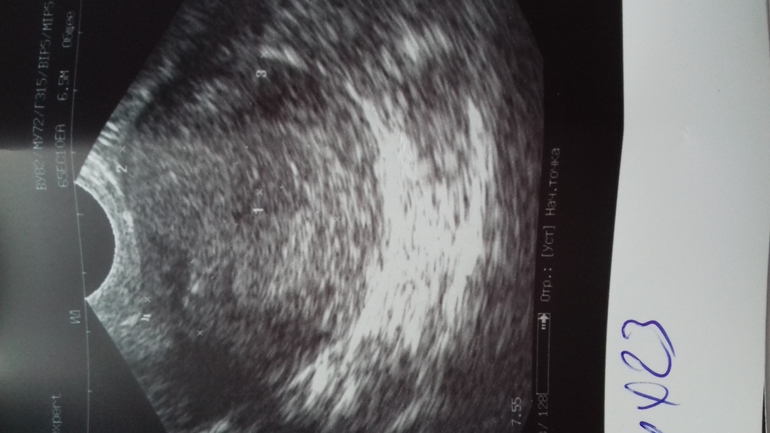

Беременность 4 недели

Но на узи я вижу какую то точку, это может быть пя?